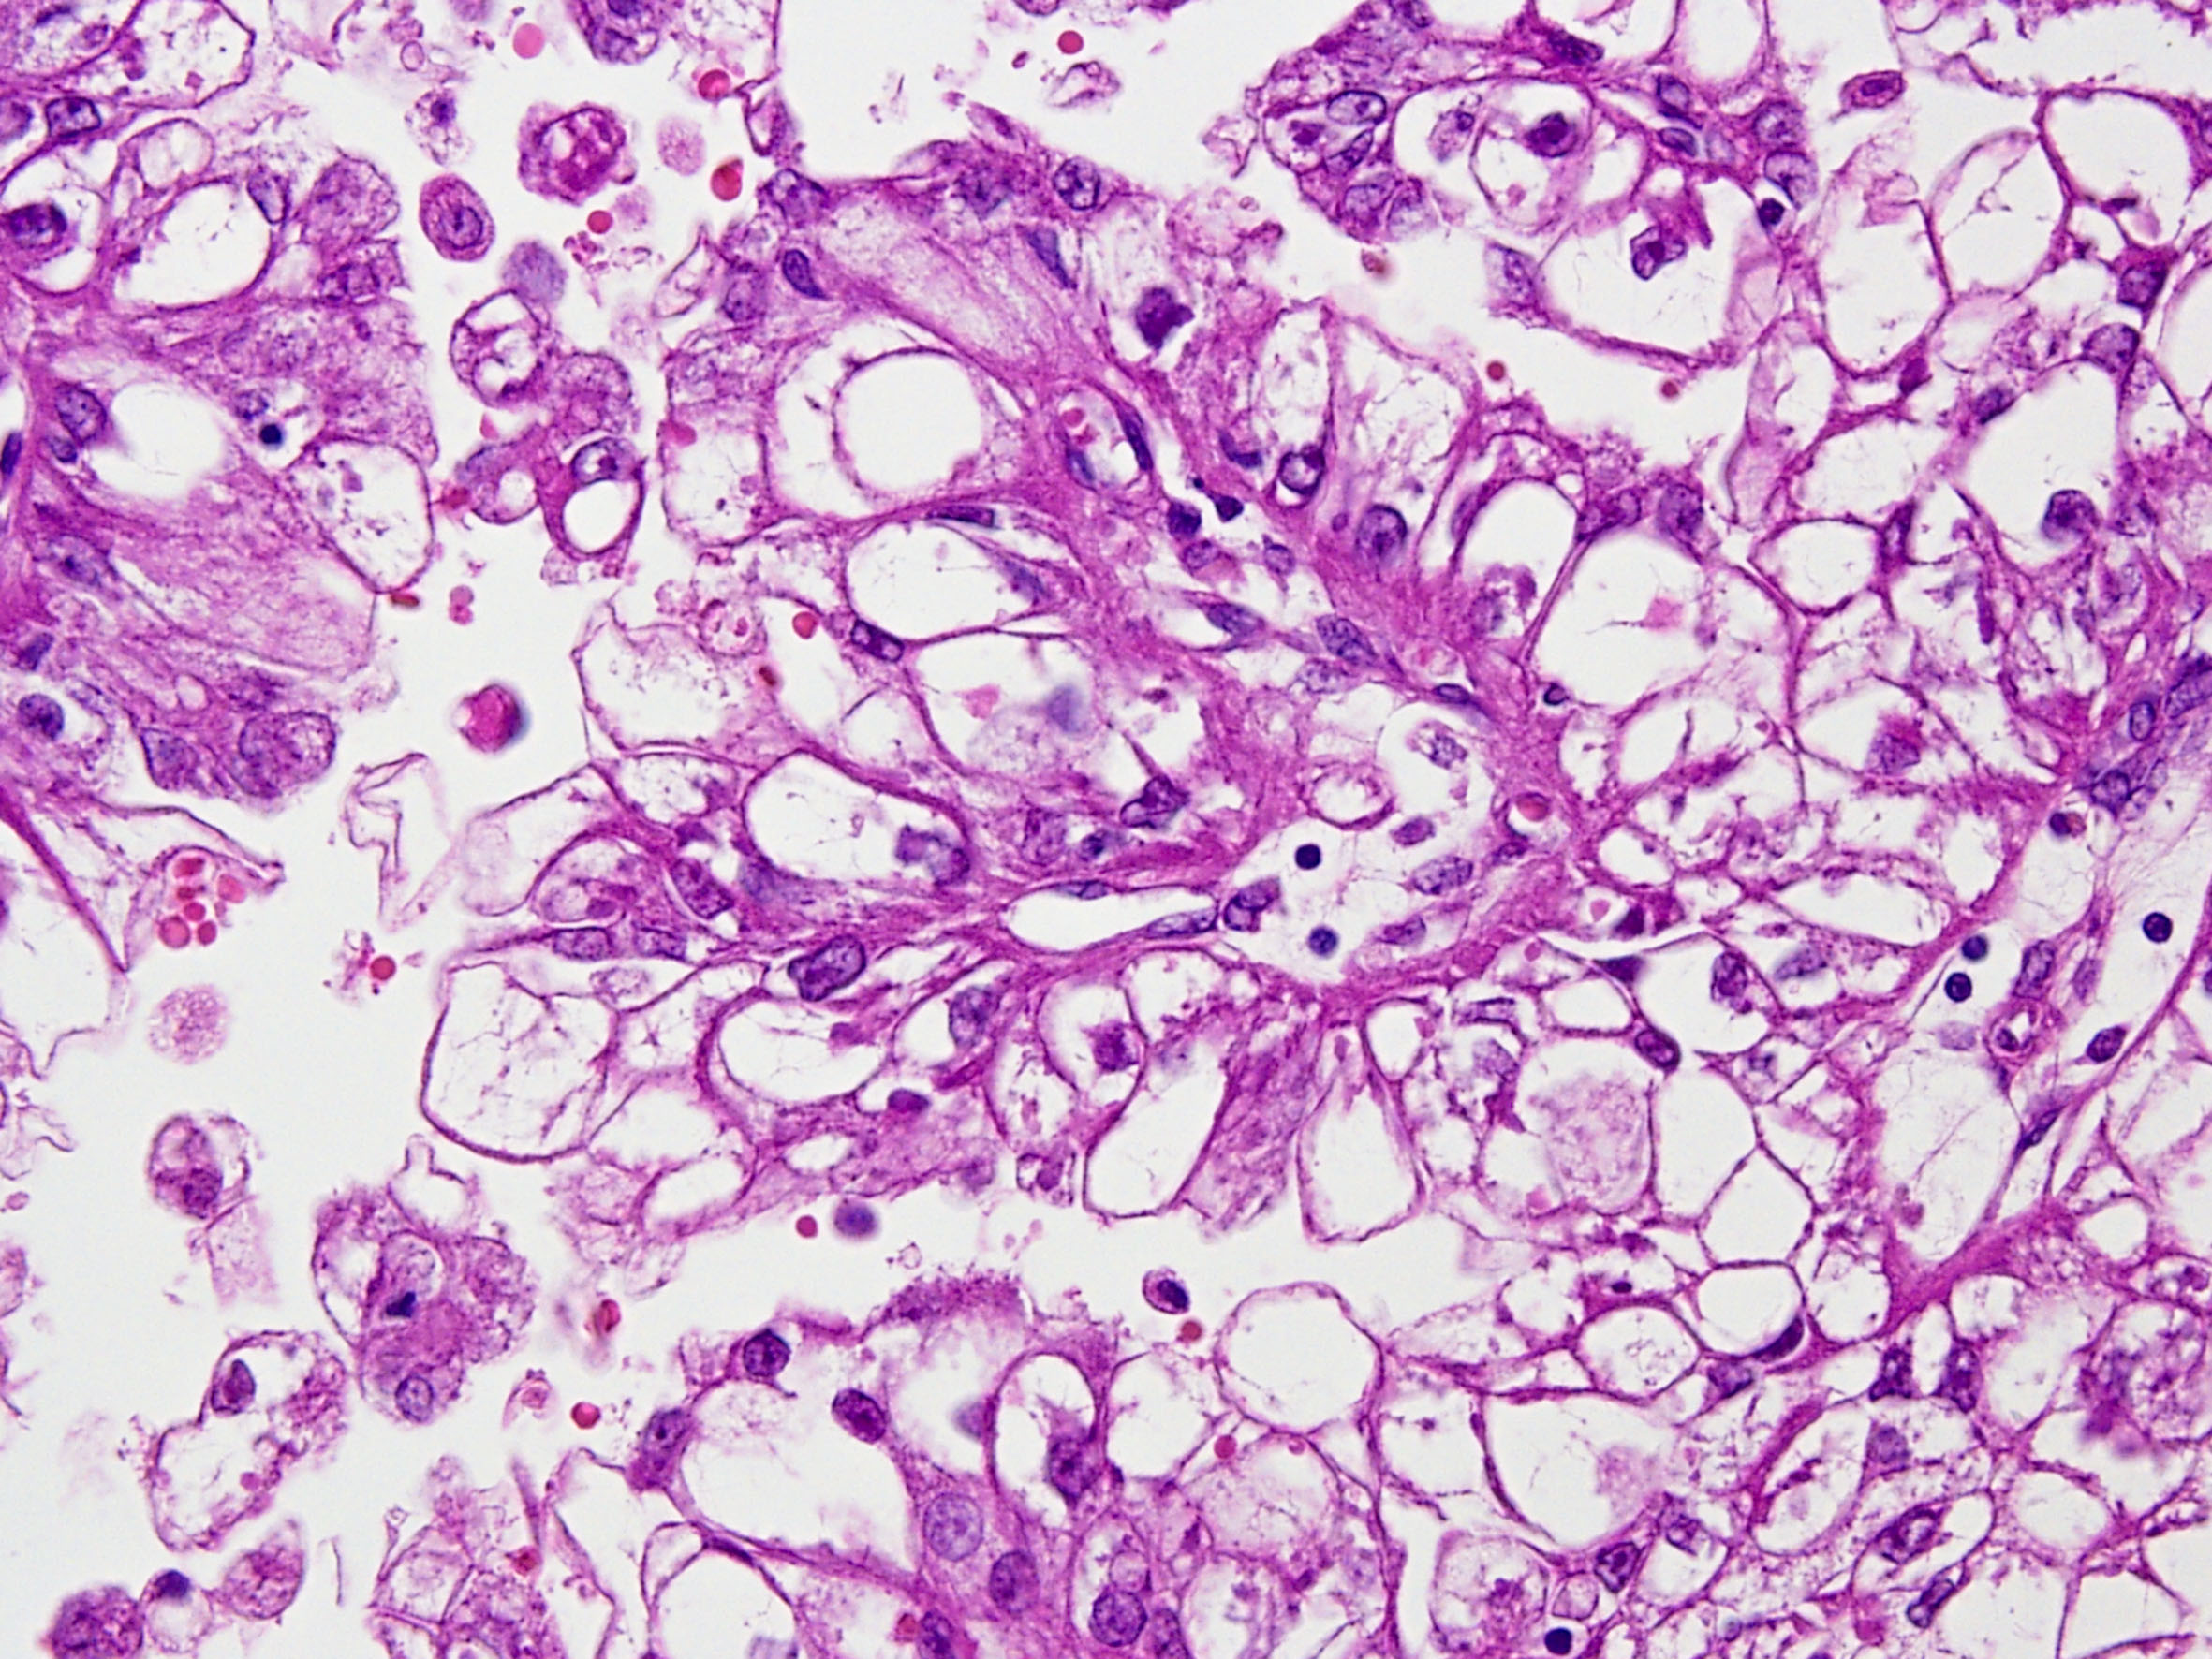

Classification of renal tumors

Case ID: 274